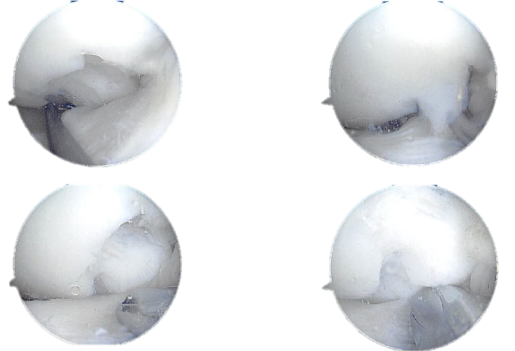

Intraoperative Arthroscopy images

The lateral meniscus was found to be extruding into the intercondylar region. Probe was introduced and tear was examined and found to be around the mid-substance with fraying of the meniscal edges.

The tear was not found to be repairable. The torn meniscus was removed using punches and shaver. The anterior horn had a meniscal cyst, which was decompressed using the shaver.

Extensive debridement of the meniscus led to a removal of 60% to 70% of the meniscus with retention of peripheral rim, part of anterior horn and anterior body and posterior horn.

The damage chondral was found to be in the posterolateral part of the lateral femoral condyle which measured to be more than 20mm x 5 mm. It was OA grade 3 to grade 4 chondral damage. The chondroplasty was performed, the damage was enough for the need of secondary reconstructive procedure for the cartilage.

Arthroscopic view tear of the lateral meniscus posterior horn